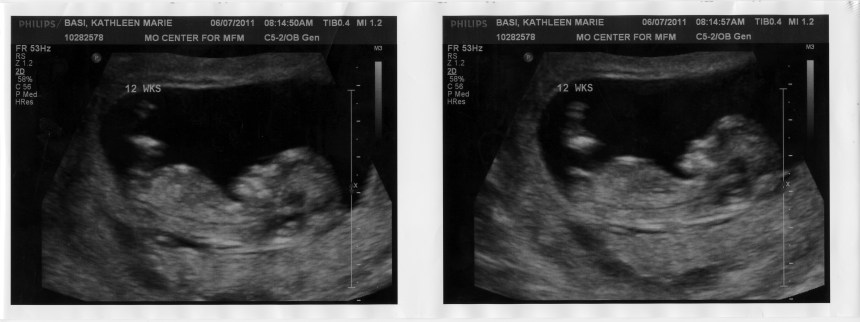

After Julianna, we decided that it was worth an ultrasound and blood test to put that niggling “what if” doubt out of our minds for the rest of the pregnancy.

Aw, beautiful baby!

Wow was that a 12 week ultrasound? The baby looks so big!

I can’t really comment on whether your ultrasounded baby is cute, but that is incredibly detailed for so early on. Wow! I guess I never knew *when* the other ultrasound photos I’ve seen were taken.